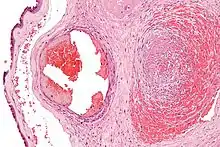

Photographie au microscope montrant la fibrine (partie amorphe rose foncé) dans une veine bloquée entourée d'une extravasation d'érythrocytes (à droite de l'image). Une artère (à gauche de l'image) est aussi visible. Coloration à l'hématoxyline et à l'éosine.